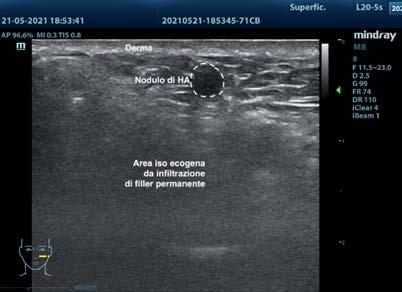

Fig. 1: nodulo di acido ialuronico in in prossimità del solco nasogenieno sinistro

CASO CLINICO Nella Fig. 1 è riportato il caso di una paziente che lamentava alla palpazione, in prossimità del solco nasogenieno sinistro, una piccola tumefazione. Anamnesticamente la paziente aveva dichiarato di aver fatto un trattamento con riferito acido ialuronico, ma che alcuni anni prima era stata già sottoposta a un altro trattamento iniettivo, però non era a conoscenza del prodotto utilizzato. Da un’attenta valutazione ecografica ad “alta frequenza” della regione è stata confermata la presenza di un deposito cistico anecoico di acido ialuronico immerso in un contesto ecografico ben preciso (area di compatta e uniforme isoecogenia descritta in letteratura con il nome di snowstorm) costituita dal precedente trattamento: chiaramente un riempimento a base di olio di silicone. Inoltre, esaminando ulteriormente le zone limitrofe (Fig. 2) e soprattutto il solco nasogenieno controlaterale, si è evidenziata la presenza di altri quattro fenomeni di incistamento più profondi e dovuti al trattamento a base di acido ialuronico, tutti con le medesime caratteristiche ecografiche (immagine semirotondeggiante quasi anaecogena con capsula ispessita iperecogena). Fortunatamente per la paziente, non si sono mai verificate complicanze superficiali più gravi come infezioni o fistole. Questa evidenza conferma l’ipotesi che il successivo trattamento filler di acido ialuronico è stato eseguito al buio, mettendo a rischio di complicanze cliniche il paziente e di complicanze medico-legali il collega.